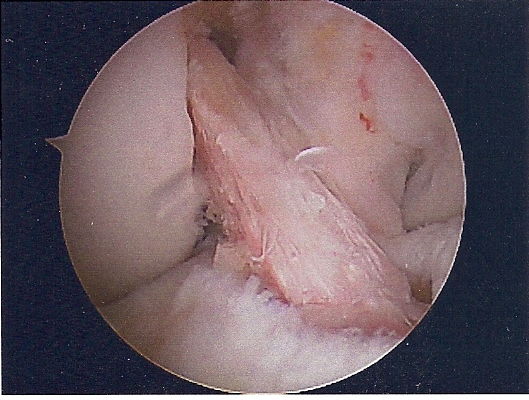

She had ACL replacement surgery on March 28th, using Bone-Patellar-Bone graft from her own patellar tendon. These are the images are scanned from pictures taken by the scope during the surgery. We were supposed to get a DVD of the procedure, but forgot to remind him on the day of the surgery. Oh well...

NEW ACL